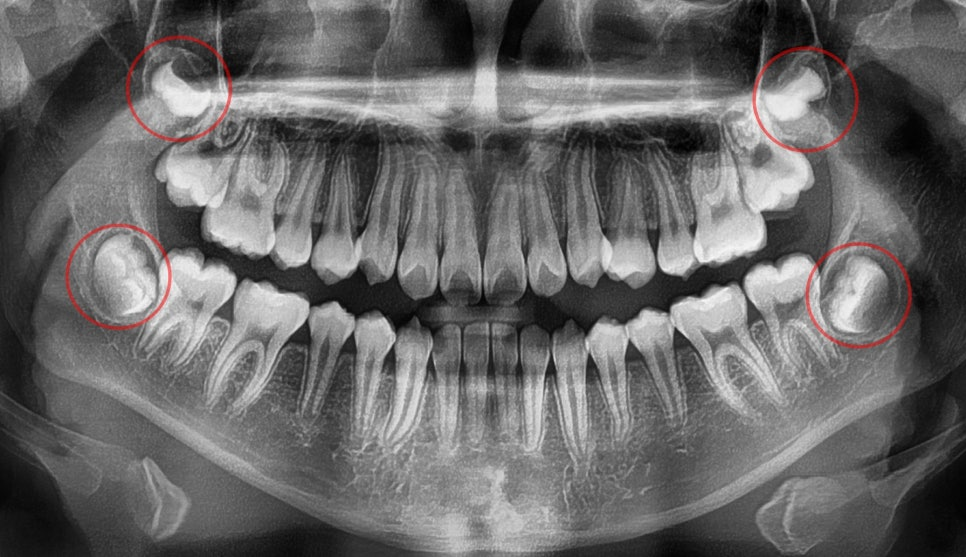

| 3. 발치 없이도 교정이 가능한가요?

23.08.17

다행히 심한 골격적 문제나 심각한 총생이 아니라면

발치 없이도 치열 개선이 가능합니다.

24.02.24

크게 삐뚤거나 배열에서 벗어난 곳이 없다면

이를 뽑지 않고 교정을 진행할 수 있다는 점이

큰 장점인데요.

| 5. 언제 치료를 시작하는 것이 좋을까요?

같이 검사할 수 있는 수완부 엑스레이 촬영(성장기 검사)

아이들의 경우 성장기에

치료를 시작하는 것이 효과적입니다.

심한 부정교합이나 틀어짐이 아니라면

성인도 비교적 짧은 기간 내에

좋은 결과를 얻을 수 있습니다.

중요한 것은 하루라도

빨리 정확한 진단을 받아보시는 것인데요.

구치 배열이나 다른 문제들도

같이 확인해야 알맞은 치료 계획을

세울 수 있기 때문입니다.